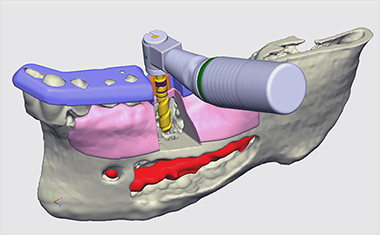

BioNaシミュレーション画像